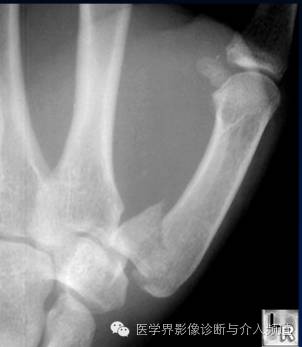

3、Bennett’s骨折

第一掌骨基底部骨折。为关节腔内骨折,非粉碎性,骨折线累及第一掌腕关节面。第1掌骨则由于拇长展肌的牵拉,导致向桡侧和背侧脱位,近端基底部骨块呈四边形。

4、Rolando 骨折

第一掌骨基底部粉碎性骨折并脱位。为关节囊内骨折,需要与Bennett’s骨折鉴别,Bennett’s骨折为非粉碎性骨折,Rolando 骨折有3个以上的骨碎块。